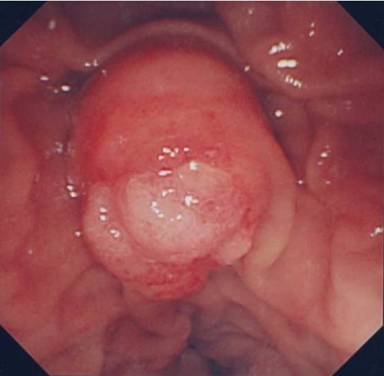

Macroscopically, the tumor measured 1.5x1.5x2 cm and the tumor surface was exposed at the papilla, showing that its surface was nodular, but there was no ulceration. Histologically, signet-ring cell carcinoma was predominant, but partially well- to poorly-differentiated tubular adenocarcinoma also existed in the lesion (Figure 3a). Signet-ring cell carcinoma arose from the ampulla of Vater, slightly involving the muscularis propria of the duodenum and infiltrating the pancreatic parenchyma. The cytoplasm of the signet-ring cell carcinoma was positive for periodic acid Schiff staining (Figure 3b). Lymphatic and vascular involvement was seen in parts, but resected lymph nodes were free from metastasis. Immunohistochemical staining was performed and both the signet-ring cells and the adenocarcinoma cells were positive for human gastric mucin (45M1) (Figure 4). Both types of tumor cells were positive for CK7, MUC1 and MUC6, but negative for CK20, MUC2 and CD10 (Figure 5). The signet-ring cell carcinoma was partially positive for CDX2 (Figure 6). The carcinoma of the ampulla of Vater was diagnosed as T3N0M0 stage IIA according to the International Union Against Cancer TNM classification. The patient did not receive chemotherapy. Six months after surgery, the patient developed pneumonia. Subsequently, the pneumonia worsened and the diabetes mellitus also deteriorated. The patient finally died from multiple organ failure due to sepsis. However, no recurrence of the signet-ring cell carcinoma was detected on repeated imaging studies.

Figure 3. Histopathological findings of the carcinoma. a. Signet-ring cell carcinoma co-existing with tubular adenocarcinoma (H&E x50). b. The signet-ring cell carcinoma was positive for periodic acid Schiff staining (H&E x50). |